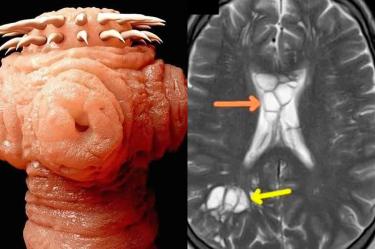

Fue entonces cómo, tras varios análisis los médicos descubrieron algo perturbador cuando observaron en las tomografías varios extraños quistes en ambos hemisferios de su cerebro, además de una severa hinchazón que confirmó sus sospechas, el hombre alojaba una tenia del cerdo en su cerebro, y no solo eso, el parasito ya había puesto huevos debajo de su cráneo lo que irritaba el tejido, por lo que fue diagnosticado con infección parasitaria neurocisticercosis.

La infección parasitaria neurocisticercosis ocurre cuando los quistes larvarios de la tenia del cerdo infectan varias partes del cuerpo y causan inflamación.